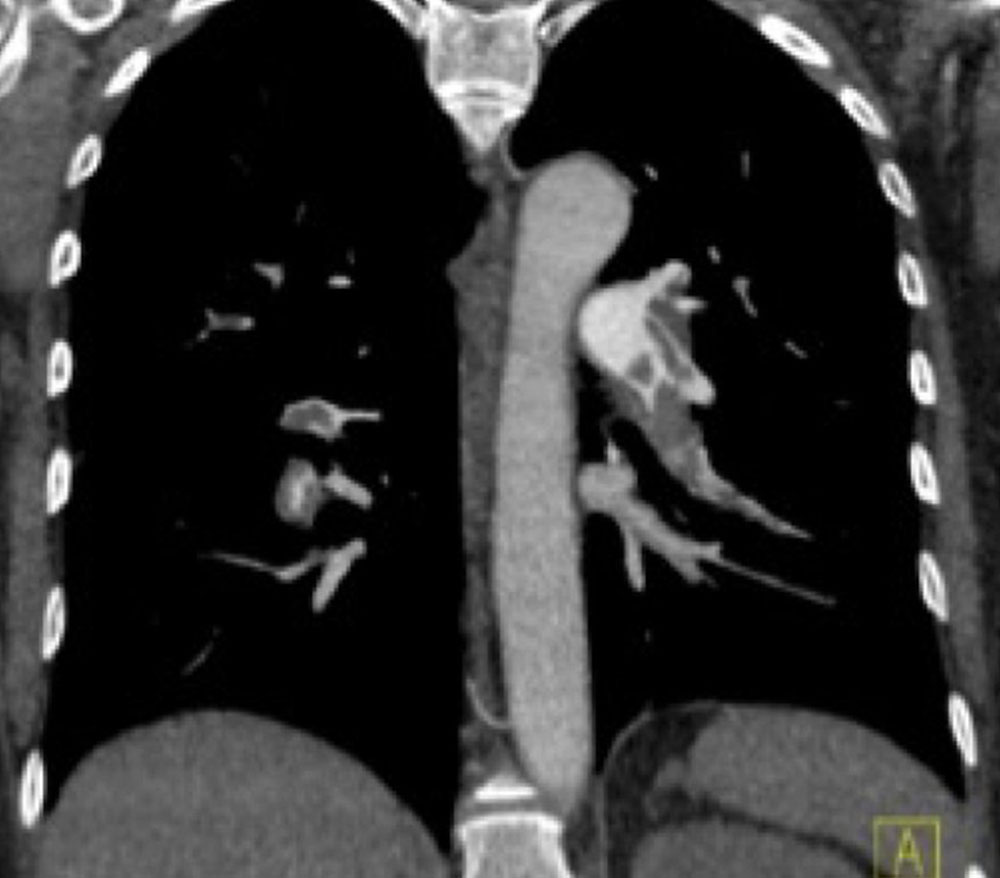

The most important, because most dangerous, complication of phlebothrombosis is the dislodgement of the thrombus via the draining veins (thromboembolism) to the central circulation. This may then lead to mechanical blockage of central vessels by the thrombus with localized thrombosis. Even more centrally after passage through the vena cava and the right heart, this blockage then affects the pulmonary arterial pathway, which is partially or completely occluded by thrombus, resulting in pulmonary embolism.

Pulmonary embolism can be sudden and prominent with massive clinical symptoms, including circulatory arrest and right heart failure due to the high flow resistance. However, pulmonary embolism is often not diagnosed immediately due to unspecific or mild symptoms. In addition, it may be completely asymptomatic in the case of smaller pulmonary emboli.

In patients with larger venous malformations who have recurrent smaller thromboembolism into the pulmonary circulation over a long period, the pulmonary arteries often become slowly and progressively occluded over a period of years with increasing flow resistance and high pulmonary arterial pressure. Chronic thromboembolic pulmonary arterial hypertension (CTPAH) may develop as a result. This complication must be avoided by adequate therapy.